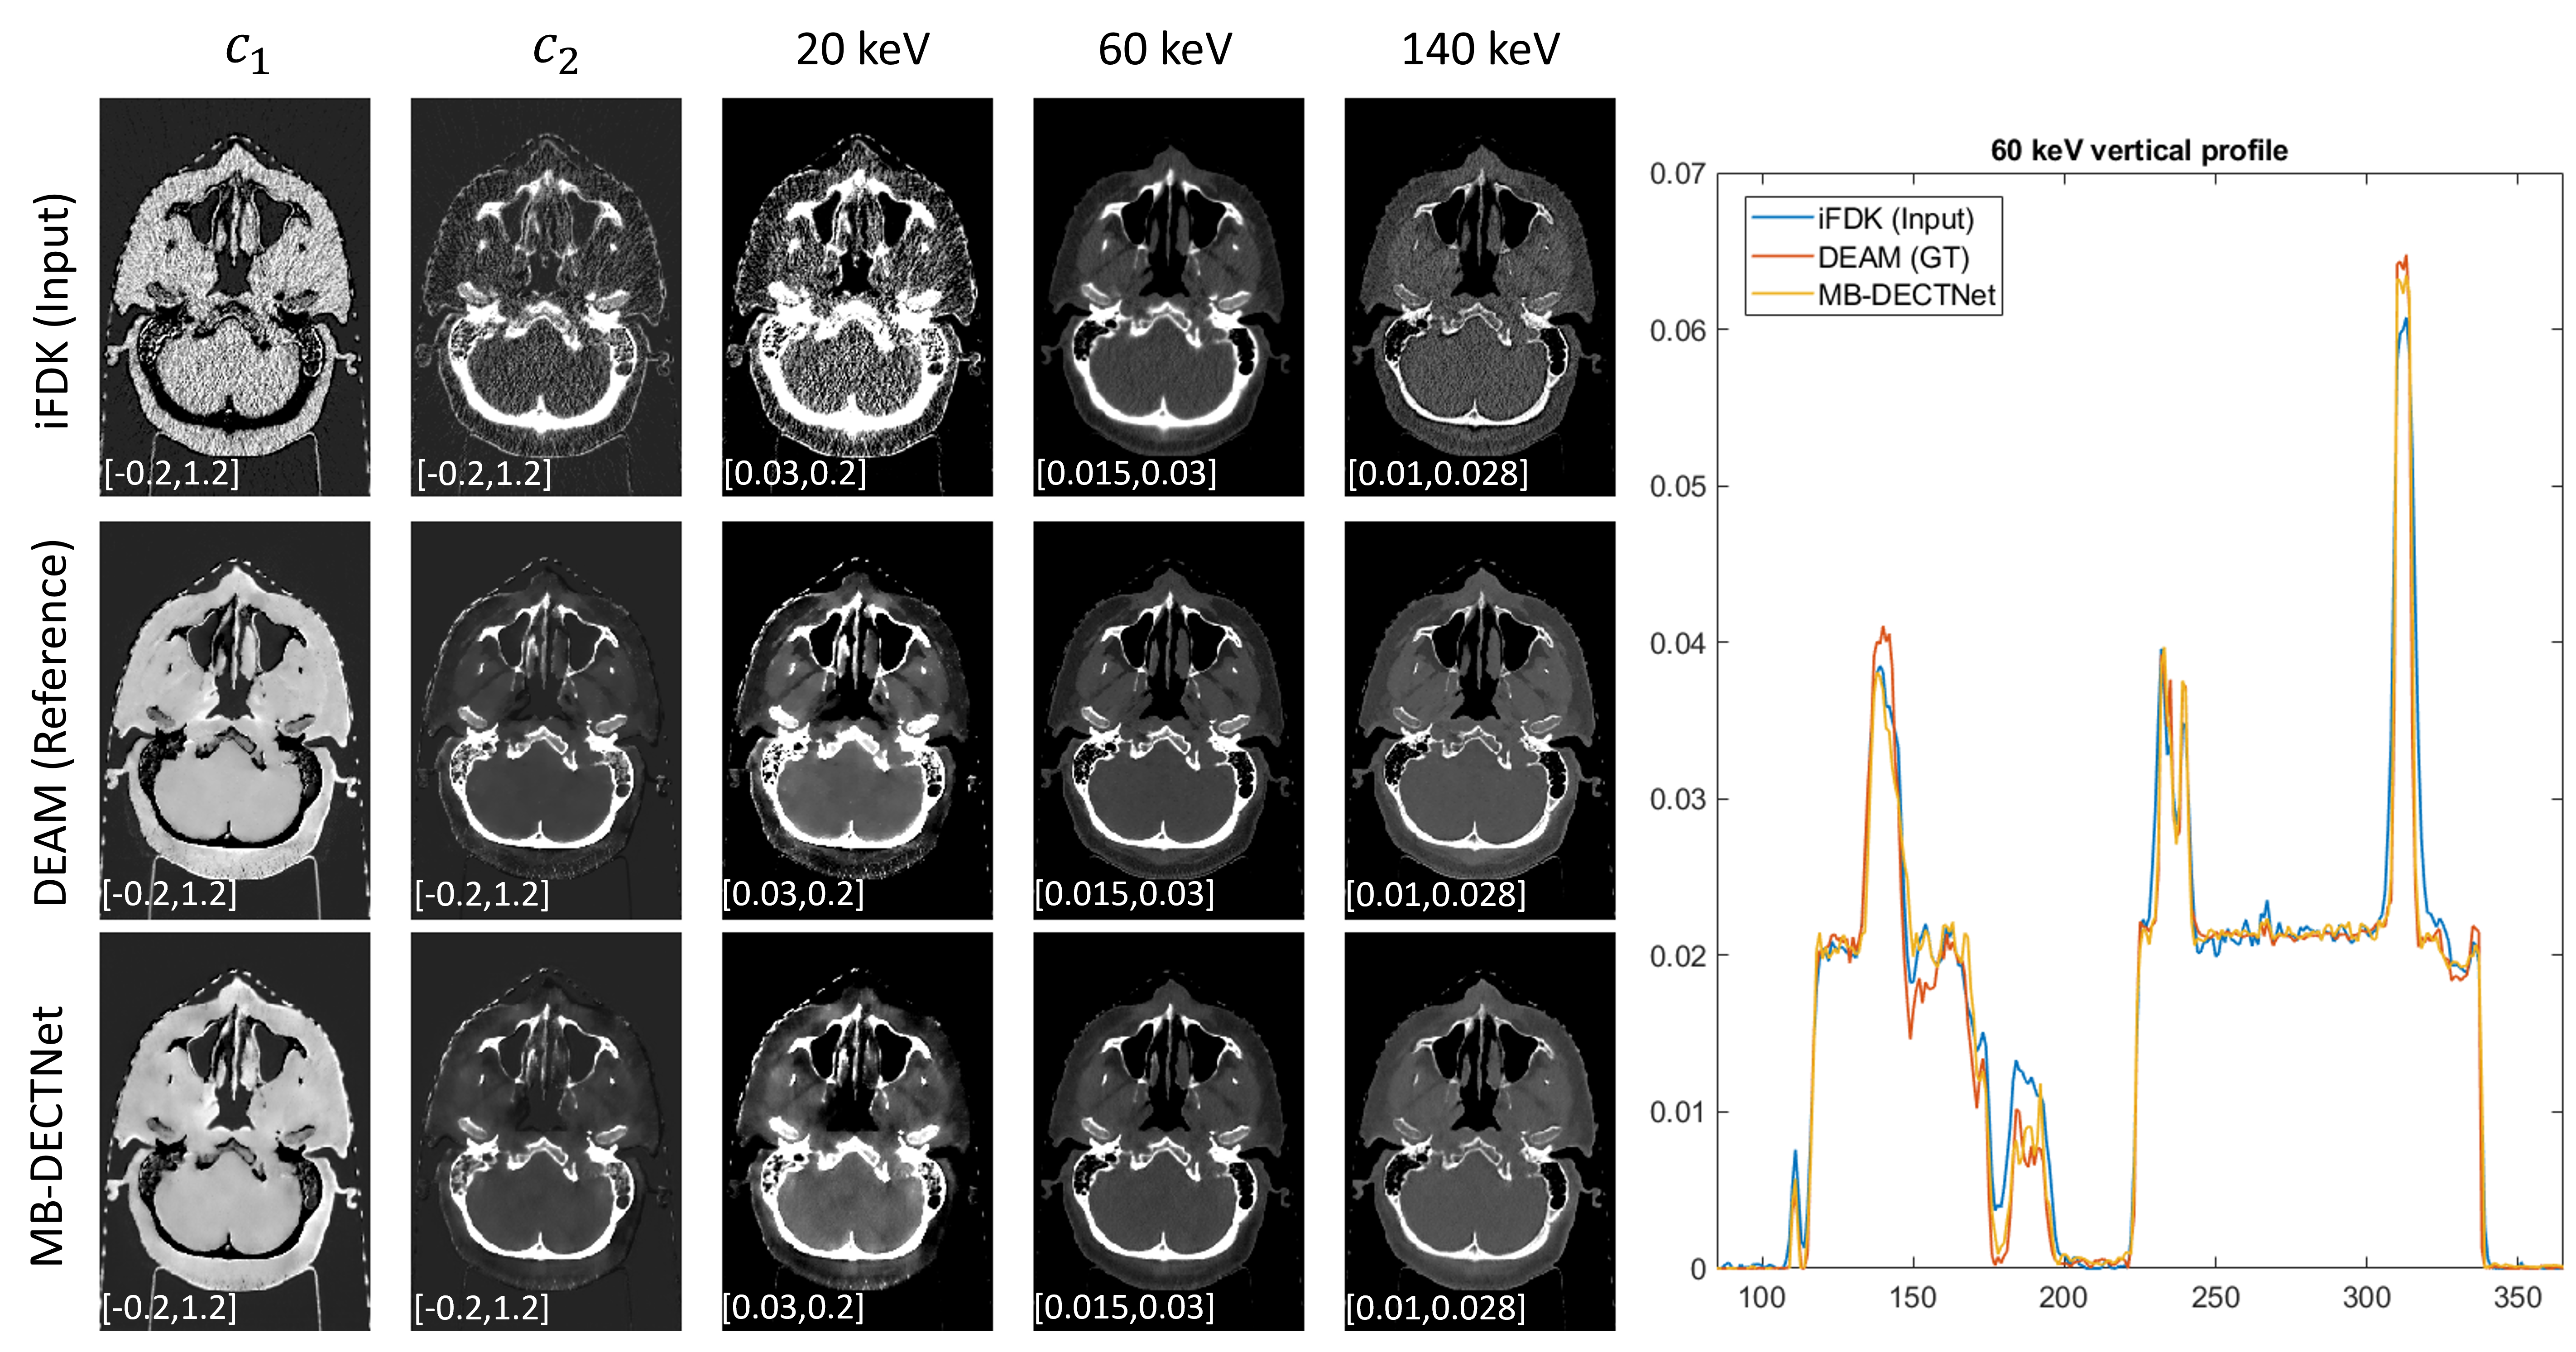

Refer to caption

Figure 3: Images and middle vertical profiles for a selected slice in the test dataset.

In the inference mode, MB-DECTNet generates a 610×610×340 image in approximately 350 seconds, which is 462-fold times shorter than the DEAM. Figure 3 shows the image of a slice as an example of the inference result from MB-DECTNet, compared to iFDK (input) and DEAM (ground truth) images. iFDK refers to the 3D analytical DECT reconstruction that combines the FDK algorithm and the iterative filtered back-projection [19]. MB-DECTNet image is much less noisy that the initial FDK estimate while preserving contrast and image sharpness. Indeed, the vertical profile suggests that MB-DECTNet improves the spatial resolution compared to the iFDK image.